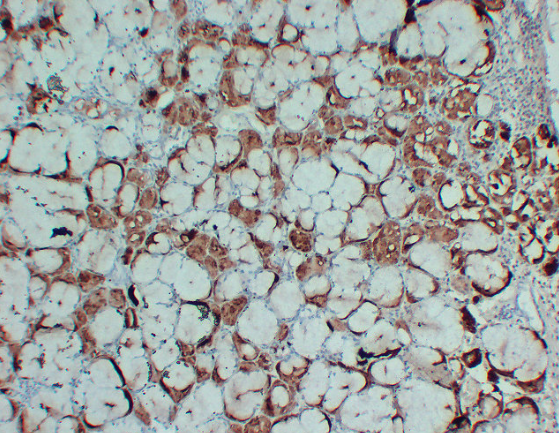

IHC (Immunohistochemistry)

(Immunohistochemistry analysis of paraffin-embedded Human Salivary glands using GCDFP 15 antibody.High-pressure and temperature Sodium Citrate pH 6.0 was used for antigen retrieval.)